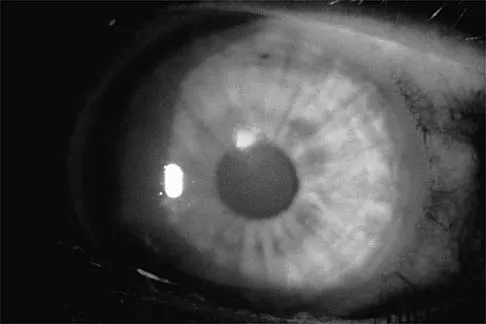

A college basketball player is struck in the eye by a player's hand while driving to the basket. Fluorescein evaluation reveals the injury shown in Figure 18. Management should consist of